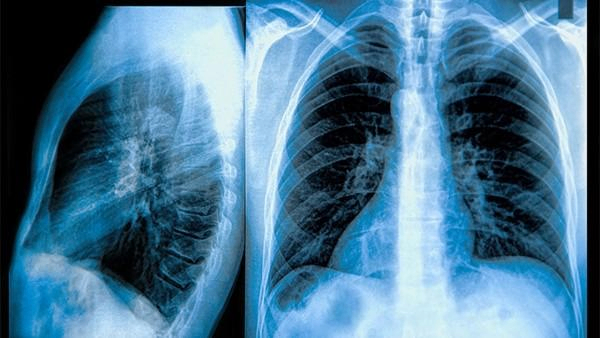

2. 诊断:

医生通常会使用影像学检查,如MRI或CT扫描,来确定是否存在脑转移。同时,对患者进行神经系统检查也是必要的。